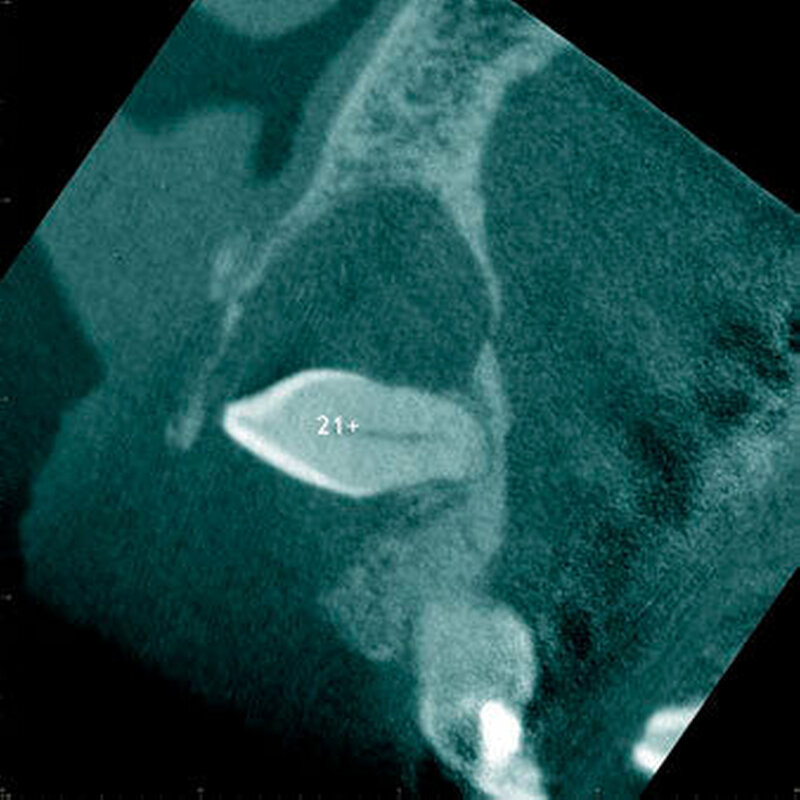

In einer aktuellen Arbeit berichteten Mossaz und Mitarbeiter (2014) über eine relativ hohe Prävalenz (22,8 Prozent) der Wurzel- resorptionen an benachbarten Zähnen, wobei besonders häufig überzählige Prämolaren zu Resorptionen führen (Abbildung 18). Für die Beurteilung der Wurzelresorptionen wurden digitale Volumentomografie (DVT) der Patienten herangezogen. In einer Studie aus China, welche ebenfalls DVT-Bilder beurteilte, wurde über eine deutlich geringere Häufigkeit von Wurzelresorptionen (1,6 Prozent) berichtet [Liu et al., 2007]. Im Gegensatz zu den Daten aus der Schweiz war Diagnose und Bewertung von Wurzelresorptionen kein primäres Ziel dieser Studie und es wurde auch keine Information über das Ausmaß der Resorptionen gegeben.

Daher könnte diese Studie leichte oder mäßige Wurzelresorptionen nicht eingeschlossen haben, was zumindest einen Teil des doch deutlichen Unterschieds in den Prozentsätzen erklären würde. Studien, welche Panoramaschichtaufnahmen zur Diagnose von Wurzelresorptionen heranziehen, berichten über Resorptionsraten zwischen 4,7 Prozent [Gündüz et al., 2008] und 7,6 Prozent [Hyun et al., 2009]. Tyrologou und Mitarbeiter (2005) berichteten sogar, dass keine Resorption im untersuchten Patientengut vorhanden waren. Allerdings wurden in dieser Studien nur Mesiodentes beurteilt, wo Wurzelresorption benachbarter Zähne eher selten vorkommen [Mossaz et al., 2014]. Generell lässt sich festhalten, dass zweidimensionale Röntgenaufnahmen für die Diagnose von Wurzelresorptionen eher ungenau sind und diese so in bis zu 50 Prozent der Fälle übersehen werden [Ericson Kurol, 1987, Heimisdottir et al., 2005; Botticelli et al., 2011; Alqerban et al., 2011a].